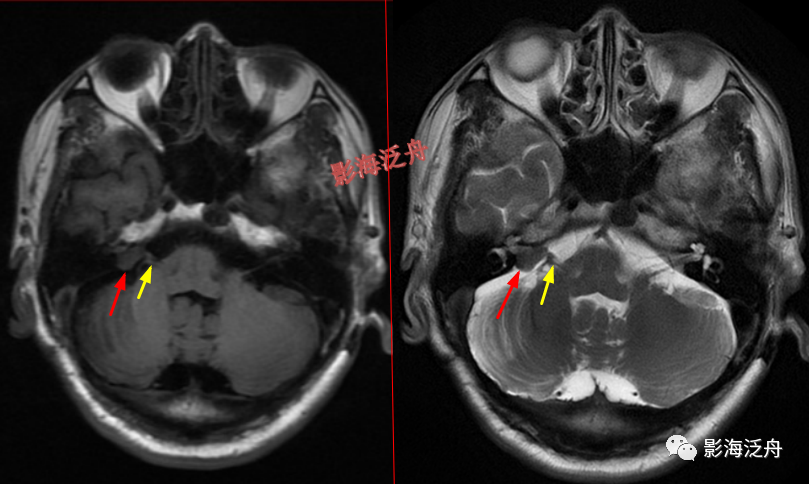

右侧CPA区(桥小脑角区)占位(红箭),呈T1WI及T2WI呈等低信号,邻近的听神经显示可(黄箭),因此倾向于诊断脑膜瘤。这个患者病史未诉听力障碍,因此平时写报告千万不要等到患者有听力障碍才去观察两侧的听神经。

右侧CPA区听神经瘤(红箭)。有些单位使用1.5T MR,对蝶鞍区及幕下结构的显示会不太理想,再加上本例患者的桥小脑角池发育的比较狭窄,不能把病灶很好的衬托出来,此时就很容易造成漏诊。

椎基底动脉迂曲走行导致邻近延髓受压,也是比较常见的,虽然算不上漏诊,但笔者认为这种病理性改变还是应当在报告中体现出来。